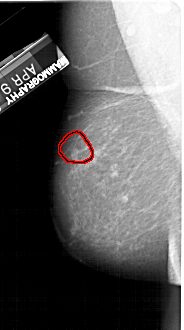

A_1435_1.RIGHT_MLO

RIGHT_MLO LINES 5326 PIXELS_PER_LINE 2851 BITS_PER_PIXEL 12 RESOLUTION 43.5 OVERLAY

FILE: A_1435_1.RIGHT_MLO.OVERLAY

TOTAL_ABNORMALITIES 1

ABNORMALITY 1

LESION_TYPE MASS SHAPE OVAL MARGINS ILL_DEFINED

ASSESSMENT 4

SUBTLETY 4

PATHOLOGY BENIGN

TOTAL_OUTLINES 1

BOUNDARY